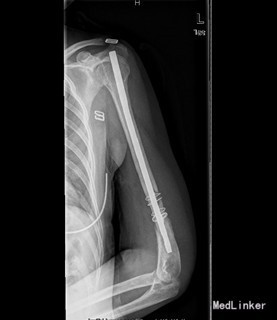

患者女,39岁,因“左肱骨骨折术后左肩关节左肘关节活动障碍6月”入院。 6月前患者外伤致左肱骨中下段粉碎性骨折,患者到当地人民医院行左肱骨骨折髓内钉及切开钢丝捆扎固定手术治疗(具体手术方式不详)。术后手术伤口恢复可,但患者左肩关节活动明显受限,并左肱骨下份肿胀严重,左肘关节活动稍受限。现患者左肩关节及左肘关节活动无明显好转,左上臂下段肿胀,皮温高。今患者到我院求进一步治疗。

查体:左上肢肱骨下段内侧有一10cm手术疤痕,下段肿胀,皮肤无明显发红。余四肢未见异常,活动无受限;左肱骨下份肿胀,未触及局限包块及波动感,肿胀区皮温高。桡动脉搏动正常。左肩关节活动明显受限,外展约20度,前伸后屈约20度,内外旋约15度,肘关节伸0度、屈45度。余关节活动无异常。 辅查:X片示左肱骨中下段骨折术后,内固定在位。

初步诊断:1、左肱骨骨折术后骨不愈合。2、左肩、左肘关节活动障碍 诊疗计划:择期行左肱骨髓内钉取出术、左肱骨骨折钢板螺钉内固定术,人工骨植骨。

术中见肱骨下份原骨折处软组织肿胀,瘢痕形成较多,有少量骨痂生成,能见原骨折端。取出髓内钉及固定钢丝后,骨折明显不稳定有假关节活动。未见明显炎性增生、渗出及坏死组织。并取随内及骨折周围部分组织送病检及培养。